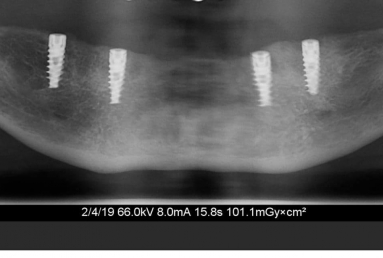

Mobile Prosthesis fixed with 4 locators on 4 Alpha BIO Nobel dental implants

Mobile Prosthesis fixed with 4 locators on 4 Alpha BIO Nobel dental implants.

The mobile prosthesis is fixed with 4 locators that firmly stabilise it. The mastication, talking and aesthetics is very comfortably and safely obtained.

After finishing the lower arch, we did the same steps for the upper arch. The mobile full maxilary prosthesis is sustained by 4 dental implants and 4 locators.